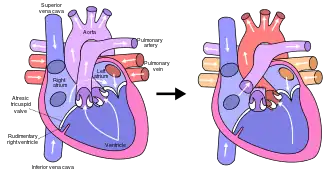

In typical anatomy, the left side of the heart receives oxygen-rich blood from the lungs and pumps it to the rest of the body. Patients with HLHS can have a number of cardiac malformations that ultimately lead to a diminutive left ventricle that is unable to supply sufficient blood flow to the rest of the body.[20] There are three main anatomic variants of the disease differentiated by either stenosis or atresia of the aortic and mitral valve.[20]

Mitral atresia and aortic atresia (MA-AA) subtype is the most severe form of HLHS resulting in no blood flow entering the left ventricle at all resulting in no possibility of left ventricular output.[20] In the mitral stenosis and aortic atresia (MS-AA) subtype blood is able to fill the left ventricle, however it is unable to be supplied to the systemic circulation via the hypoplastic ascending aorta.[20] Lastly, the mildest form is the mitral stenosis and aortic stenosis (MS-AS) subtype.[20] In these patients although the left ventricle is able to supply some blood flow to the rest of the body the overall left ventricular systemic output remains inadequate.[20]

In all of these cases blood is unable to be pumped to the rest of the body by the left ventricle. The neonate is reliant on blood flowing through an atrial septal defect to mix oxygenated and deoxygenated blood, and on a patent ductus arteriosus to allow blood to reach the aorta and the systemic circulation via the right ventricle. This is what defines HLHS as a "single ventricle" defect.[15]

The three-stage procedure is a palliative procedure (not a cure), as the child's circulation is made to work with only two of the heart's four chambers.